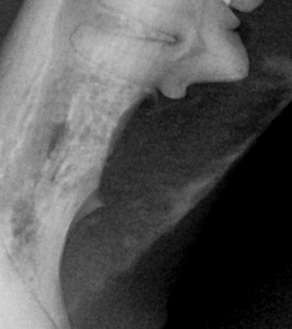

덴탈 X-ray를 통해 치아 내부 상태를 정확히 파악한 후, 아이에게 불필요한 고통 없이 최선의 결정을 내릴 수 있도록 안내합니다.

BEFORE

AFTER